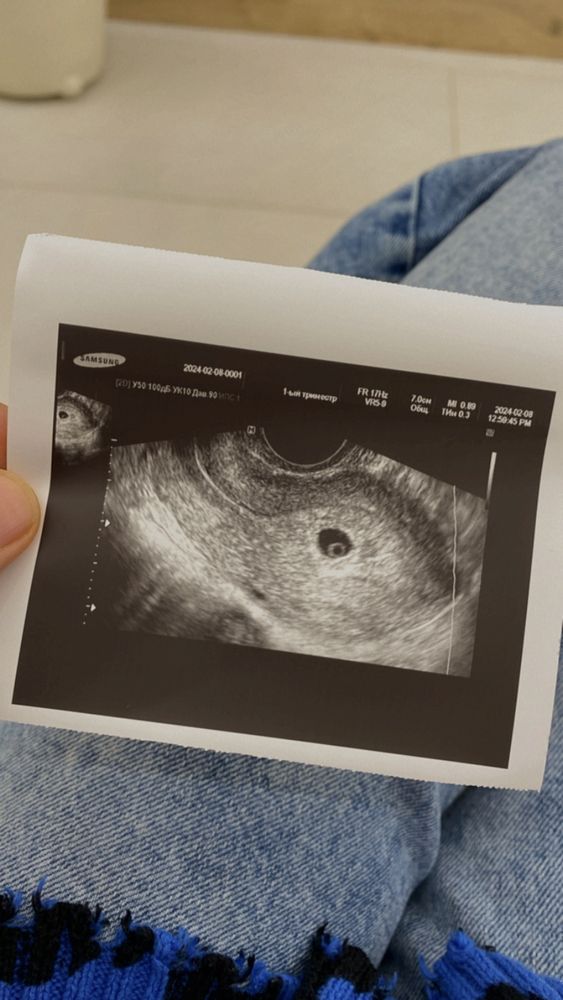

Сходила на узи

Замершая беременностьСходила на узи поставили 3-4 недели сердцебиения еще нет

придти через 10 дней

Вот такое милое яичко , еду в автобусе и меня переполняют какие то новые чувства